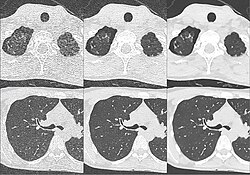

Kombination aus multiplanarer Reformatierung und sliding thin slab. Der Bildkursor befindet sich im rechten Lungenflügel. Die sts-Bildstapel werden in Form von MIP-Darstellungen gezeigt (STS-MIP).[52] Links oben befindet sich eine VR-Darstellung der Lunge; sie zeigt einen Blick auf die koronal an Kursorposition geschnittene Lunge. -